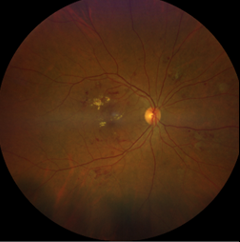

Foto 2. Mitteproliferatiivne DR

Diabeedi korral kahjustab kõrge veresuhkur võrkkesta väikeseid veresooni. Veresooned  võivad sulguda või muutuda lekkivateks. Diabeetiline retinopaatia (DR) jaotub mitteproliferatiivseks diabeetiIiseks retinopaatiaks (NPDR) ja proliferatiivseks diabeetiliseks retinopaatiaks (PDR). Selline klassifikatsioon põhineb võrkkesta veresoonte kahjustustel ja uute võrkkestaväliste veresoonte tekkimisel ning on aluseks õigeaegsele diagnoosile ja ravile.

Mitteproliferatiivne diabeetiline retinopaatia (NPDR) jaotatakse kolme raskusastmesse: kerge, mõõdukas ja raske. Kerge ja mõõduka vormi korral tekivad veresoonte laiendid ja väljasopistused (mikroaneurüsmid), võrkkestasisesed verevalumid (intraretinaalsed hemorraagiad) ja veres leiduvate komponentide (lipoproteiinide) ladestused.

Raske vormi korral lisanduvad eespool loetletud muutustele võrkkesta veenide laienemine ja ühendusveresooned veeni ja arteri vahel (IRMA). Eelkirjeldatud muutusi võib silmapõhjas näha hulgaliselt.

Haiguse arenedes võivad tekkida uudisveresooned (proliferatiivne retinopaatia). Uute veresoonte sein ei ole täiusliku ehitusega, vaid lekkivam ja rabedam. Silmasisesed verevalumid on uudisveresoonte korral tüüpiline tüsistus, mis raskematel juhtudel võib vajada kirurgilist ravi.

Sellised veresooned soodustavad sidekoe teket (proliferatsioon), mis võib viia võrkkesta irdumiseni silmas ja nägemise kaotuseni. Proliferatiivne retinopaatia (PDR) võib kujuneda ka ilma eelnimetatud sümptomite ja nägemisteravuse halvenemiseta.